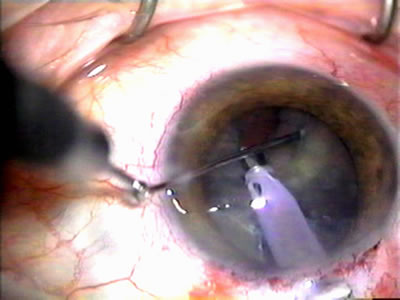

In years past, patients with both cataract and glaucoma frequently provided overwhelming surgical challenges for the ophthalmologist. The ability to carry out phacoemulsification through a 3.2-mm corneal incision along with inserting a foldable IOL is a vast improvement over 11-mm incisions that were common a decade ago (Fig. 1). The anatomical and inflammatory changes to the eye are less with small incision techniques, improving the likelihood of success with concomitant glaucoma surgery. Pharmacologic inhibition of fibrosis along with postoperative wound revision increases the long-term success rate of filtration surgery when combined with lens extraction. (Fig. 2). The learning curve may be steep at times, but the blending of cataract and glaucoma surgical skills slowly falls into place as the surgeon constantly learns and upgrades his or her technique.

Fig. 1. The anatomic advantage of small incision cataract surgery for the glaucoma patient. A. Long-term bleb function with a large cataract incision is difficult to achieve with either ECCE-trabeculectomy or trabeculectomy followed later by ECCE. This bleb failed to form sufficiently when combined with large incision ECCE. The inflammation, bleeding, and long-term wound healing with stimulation of fibroblasts associated with this technique are more likely to cause bleb failure. In addition, the increased iris manipulation necessary to deliver the nucleus and subsequent iris repair adds to the long-term breakdown of the blood aqueous barrier. B and C. Two-site phacotrabeculectomy has the advantage of small incision cataract surgery combined with separate site trabeculectomy. The incision size is one third the size of the standard ECCE. The inflammation is less severe, and cataract wound healing is confined to the temporal area. Visual rehabilitation with phacoemulsification and foldable IOL is much faster. Phacoemulsification allows successful lens extraction even in the unfriendly environment of a smaller pupil compared with ECCE. The trabeculectomy is performed in an entirely different site, well away from the wound healing associated with temporal phacoemulsification. The likelihood of this filter functioning long-term is greater than with ECCE-trabeculectomy. D. The surgeon also has the option of single-site phacotrabeculectomy with foldable IOL. Both the lens extraction and trabeculectomy are performed through one small 3.5-mm limbal incision.